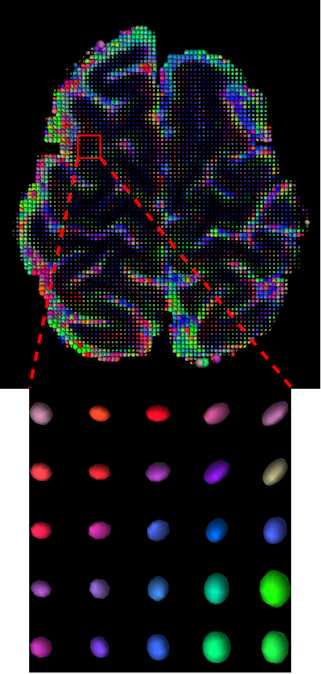

III-D Qualitative Results

The visualization of inpainted results (showing the whole diffusion tensor for each voxel) generated from different models are demonstrated in Figure 3, where the tensor is represented in RGB coding that colours red, green and blue represent diffusion in the x, y, and z axes respectively. One typical example of reconstruction in the disrupted ROIs has been zoomed for visualization. Compared to the ground truth, TW-BAG is able to generate more distinct orientations following the original distribution and intensity across sagittal, coronal and axial views, which could demonstrate water diffusivity (denoted by eigenvalues of tensor model) more accurately. As indicated in Figure 4, the boundaries and textures of the FA map for TW-BAG are less blurry than the other competing models, validating the effectiveness of TW-BAG from a neuroscience perspective.